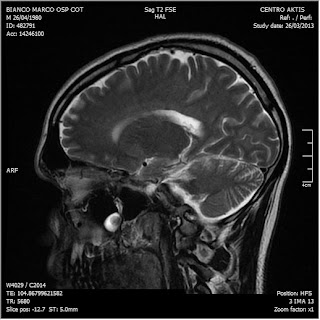

26/03/2013. Ritorna a controllo al Cotugno dove effettua nuova RM con MdC

RM del 26/3/2013